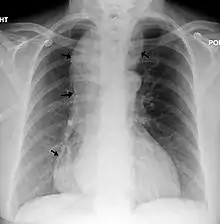

| Chest x-ray of an individual with achalasia. The arrows point to the areas of extreme esophageal dilation. | |

Symptoms of achalasia can be detected by fluoroscopy during barium swallow or oesophageal manometry.[4]

Achalasia

Barium swallow

A positive barium swallow will display the narrowing of the distal oesophagus in a 'bird beak' or 'champagne class' fashion, aperistalsis, minimal LES opening and oesophageal dilation as the main indicator of the disease.[4][5] Minimal barium will be present in the stomach.[5] However, these diagnostic findings are not always present in the early onset of the disease and so a normal oesophagogram is not an indication of a lack of disease.[5]

Oesophageal manometry

Patients with the vigorous achalasia variant of the disease, do not express dilation.[4] Manometry is the best, most sensitive method in these cases as it can diagnose abnormalities related to achalasia based on basal pressure, without the need for the manifestation of dilation.[4][5] Aperistalsis and a poorly relaxed and hypertensive LES is required for a positive diagnosis.[5]